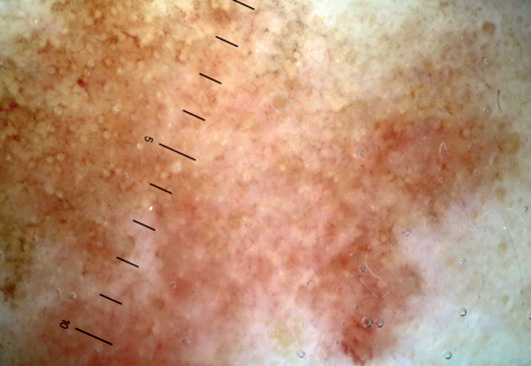

Дерматоскопические изображения для последующего анализа были получены с помощью дерматоскопов DermLite DL3N, Heine DELTA 20(T), адаптеров и фотоаппаратов Nikon 1 J1, Canon 750D. Фотографии сделаны в поляризованном режиме дерматоскопа с использованием ультразвукового геля в качестве иммерсии.

- 54 пациента с актиническим кератозом, у которых получены дерматоскопические изображения 85 элементов актинического кератоза. Диагноз установлен на основании данных анамнеза, клинической и дерматоскопической картин. В случае получения дерматоскопических признаков актинического кератоза 3-й степени диагноз был подтвержден патоморфологическим исследованием;